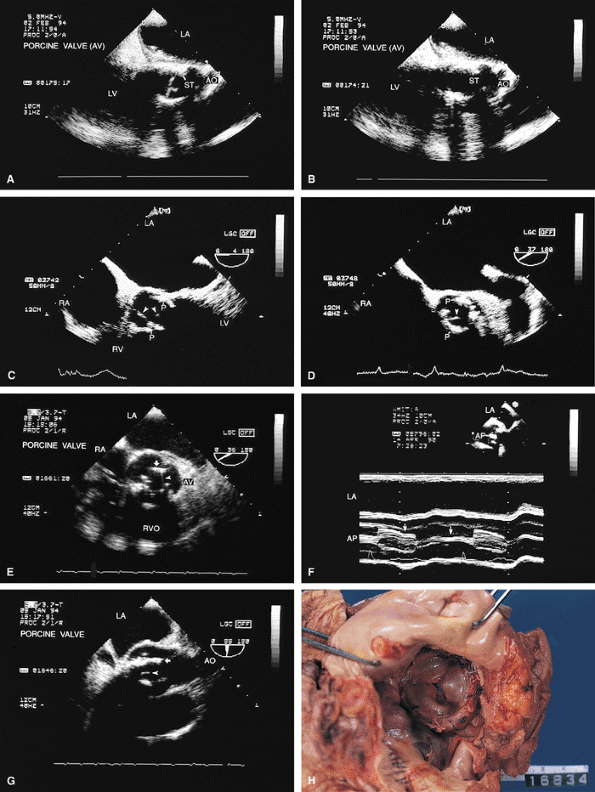

FIGURE 5.18. Porcine mitral prosthesis: normal. The porcine prosthesis is shown in the closed position (A, B; arrow in B) in systole and in the open position (arrow in C) in diastole. D. The porcine prosthesis imaged in short axis. E. Mitral prosthetic (P) inflow with a localized area of flow acceleration on the atrial side of the valve. F. A systolic frame demonstrates absence of regurgitation through the prosthesis mitral prosthesis (MP). G. ST, prosthetic stents in left ventricle (LV); S, sutures on the atrial side. AV, aortic valve; LA, left atrium; MV, mitral valve; LAA, left atrial appendage; RA, right atrium; RV, right ventricle. |

|

FIGURE 5.19. Porcine mitral prosthesis: stenosis and regurgitation. A. A large diastolic flow acceleration (arrowheads) on the atrial side of the prosthesis (P), suggesting the presence of obstruction. B. Thickening and calcification of the prosthesis resulting from degeneration. C. A decreased slope of the diastolic velocity profile with a measured mitral valve area (MVA) of 0.9 cm2 measured by the pressure half-time technique, indicating significant obstruction. D. Associated severe valvular mitral regurgitation (MR) (arrowheads). Images B through D are from the same patient. AO, aorta; LA, left atrium; LV, left ventricle; PA, pulmonary artery; RA, right atrium; RV, right ventricle; RVO, right ventricular outflow tract. |